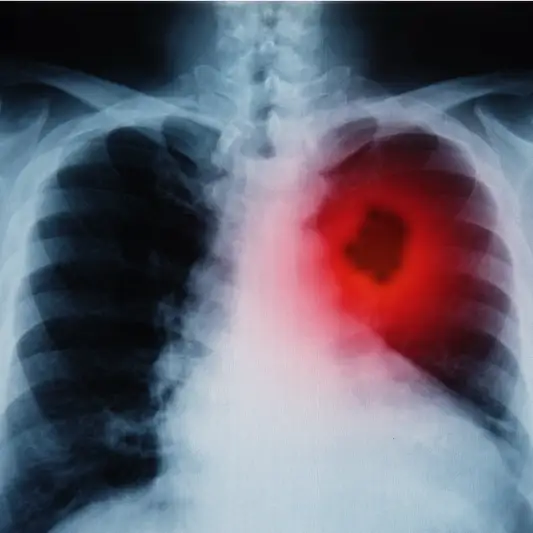

폐암 수술은 환자들에게 중대한 물리적 및 정신적 영향을 미칩니다. 수술 후 이러한 영향을 완화하고 성공적인 회복을 위해서는 알맞은 관리와 후송 기간이 필요합니다.

첫째로, 수술 후에는 상처의 치유와 감염 예방을 위해 적절한 처치가 필요합니다. 이는 정기적인 상처 관리 및 안티바이오틱의 사용을 포함합니다.